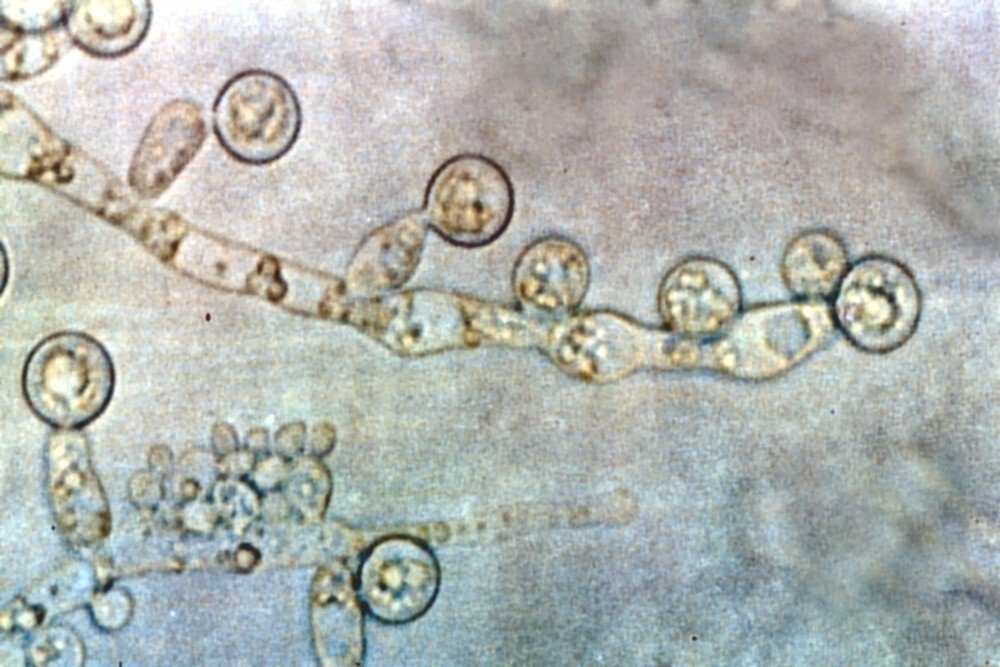

Candida albicans, a yeast (fungus) that commonly causes infections in humans. Image by  Graham Colm. Creative Commons Attribution Share Alike 3  License. https://creativecommons.org/licenses/by-sa/3.0